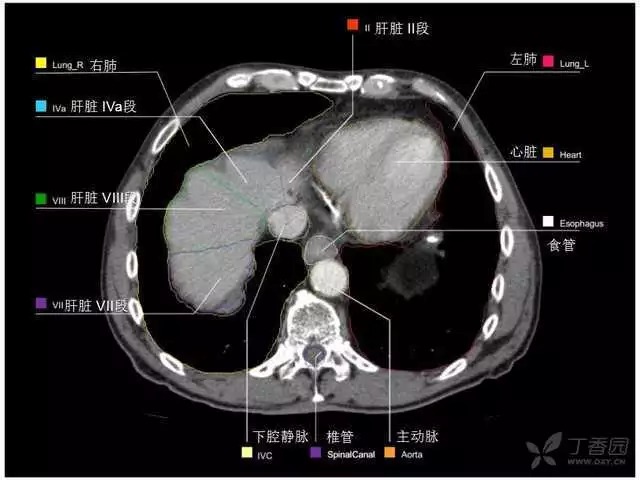

腹部肝脏高清CT断层的图谱

全腹部高清CT图谱,淋巴结彩色图谱,血管解剖图谱大汇总!

肝段,肝内管道的分布规律

美国放射学会ACR官网,对肝脏的区域和节段解剖学概述